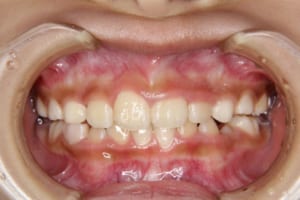

前歯のクロスバイト(部分的に前歯のかみ合わせが逆になっている)を伴う小学生の女の子の治療例

治療前

| 年齢・性別 | 8才 女性 |

|---|---|

| 主訴 | 上の歯が後ろに引っ込んでいる |

| 治療内容 | 顎の成長を利用して子供の矯正治療を行いました |

| 使用した装置 | 舌側弧線装置(リンガルアーチ) スライディングアーチ 緩徐拡大装置 |

| 治療回数 | 10回 |

| 治療期間 | 1年3か月 |

| 抜歯および非抜歯 | 非抜歯 |

| 費用(保定除く) | 405,000円(税込) |

| リスク・副作用 | 主なものとして、 ・歯の痛み ・虫歯/歯周病 ・口内炎 ・発音障害 ・食事の制限 ・歯肉の退縮(歯茎が下がる) ・知覚過敏 ・歯根吸収(歯の根が短くなる) ・金属やゴムのアレルギーの発症 ・歯髄壊死(歯の神経が死んでしまう) 等のリスクが考えられます。 |

| その他/備考 | 少ない回数、短期間で矯正治療を終えることができ、大変満足していただけました。 治療後、親御さんも矯正治療を希望され治療を開始しました。 |